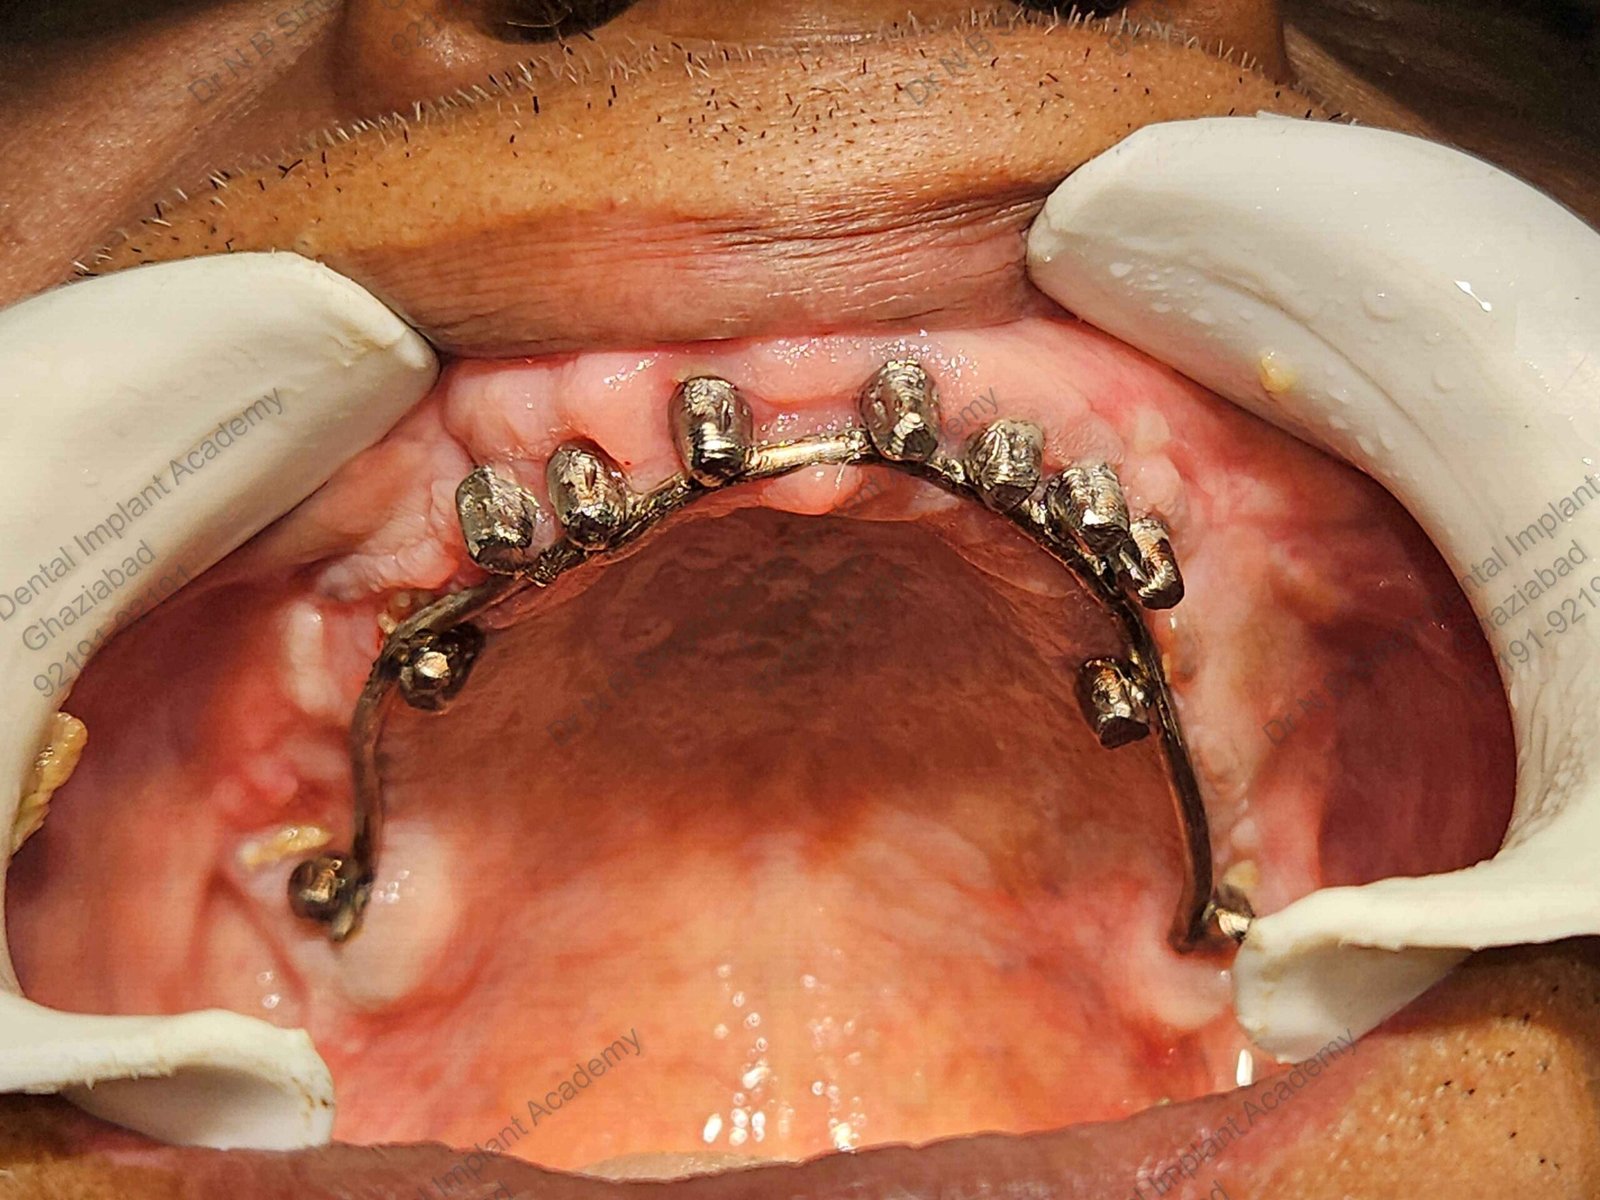

C1005 zygomatic basal implant full mouth – Ali Hasan 4